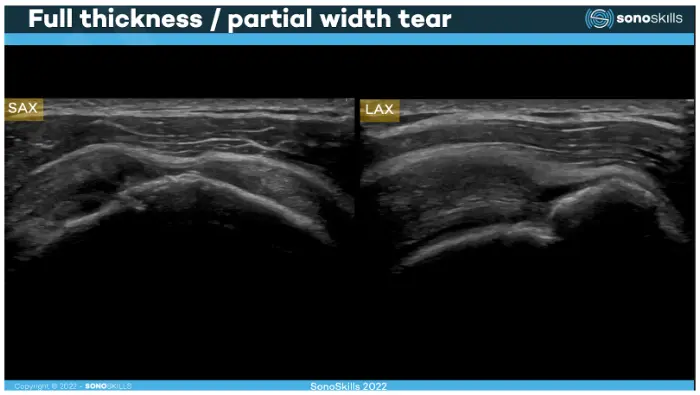

Side-by-side images of a shoulder ultrasound. The left image (2A) shows a grayscale ultrasound scan with layered soft tissues above the curved surface of the humerus bone. The right image (2B) shows the same anatomy with color overlays and labels identifying the subcutaneous layer, deltoid muscle, infraspinatus muscle, and the humerus bone below. Three-panel illustration showing a shoulder joint and an ultrasound-guided injection. The top panel displays the shoulder joint anatomy with the humeral head and surrounding structures. The middle panel shows a needle entering the shoulder while an ultrasound probe is placed on the skin to guide the injection. The bottom panel presents the ultrasound image where the needle is visible approaching the joint. Two ultrasound images labeled SAX and LAX under the title “Full thickness / partial width tear.” The scans show the shoulder tendon with an irregular gap indicating a rotator cuff tear. The images demonstrate how the tear appears in both short-axis and long-axis ultrasound views. If you are searching for accurate diagnosis of joint or muscle pain in Virginia Beach, you may have heard about MSK ultrasound. At Barr Center for Innovative Pain & Regenerative Therapies, musculoskeletal ultrasound is one of our most useful diagnostic and treatment tools for painful conditions.